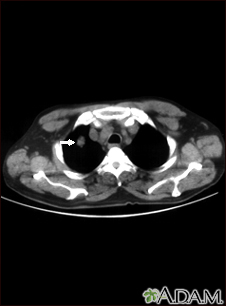

Pulmonary nodule, solitary - CT scan

This CT scan shows a single lesion (pulmonary nodule) in the right lung. This nodule is seen as the light circle in the upper portion of the dark area on the left side of the picture. A normal lung would look completely black in a CT scan.